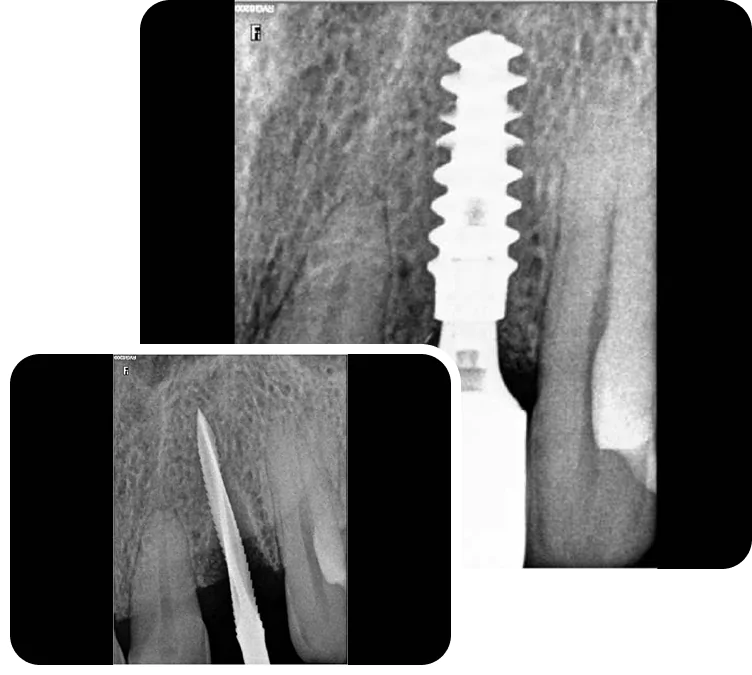

Smilex Advanced Dental Care proudly offers world-class Same Day Dental Implants Treatment in India, enabling you to regain full dental function in just one visit. Whether you've lost a single tooth or multiple, our expert implantologists use advanced digital scans, CBCT imaging, and CAD/CAM-supported restorations to provide precise, long-lasting results.

Same Day Implantology is an advanced dental procedure that allows for the replacement of missing teeth with dental implants in just a single appointment. Unlike traditional methods that involve multiple visits and a lengthy healing period, Same Day Dental Implants In India offer a more efficient and convenient solution, providing immediate results. This process involves precise digital planning to ensure the correct placement of implants, improving both the speed and success rate of the procedure. Additionally, if you’re considering a complete smile transformation, understanding the Full Mouth Dental Implant Cost In India will help you make an informed decision about this quick and effective treatment option. With modern technology and expert care, you can restore your smile in no time while maintaining long-term oral health.